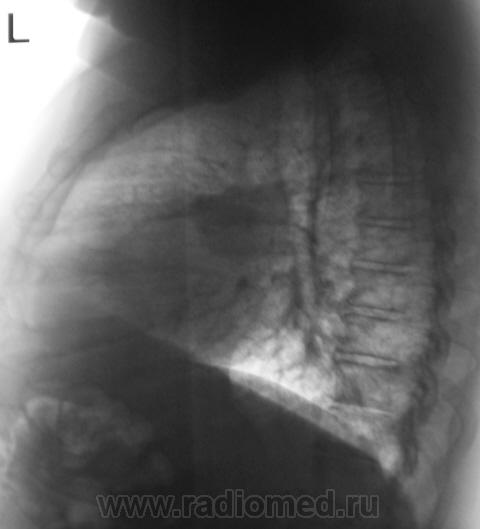

Начало 2008 года. При расшифровке флюорограмм, пациента "взяли на контроль", заподозрили периферический рак левого лёгкого (по "прямой" флюорограмме). Вроде-бы все правильно и логично?

Но мы, пациента дообследовали, рентгенография и томография (аналоговая), высказали мнение о наличии "опухолевого роста" и рекомендовали консультацию онколога, и пациент "поехал" туда, куда послали. Снимков (тех первых) предоставить не могу, остались там, куда "послали". Выписка "рекомендовала" понаблюдать....

В апреле 2009 года пациент пришел "для динамического наблюдения" - серия 2.

После повторного дообследования (апрель 2009 г) - 2 серия изображений, мы были твердо уверены, что пациент взят на учет..., но не тут-то было. В пятницу рентгенолаборант флюорографа попросил подойти и "глянуть снимок"...

Оказывается "данный" пациент направлен для прохождения профилактической флюорографии..., так как надо было поменять водительские права...?

2. Конечно, мы на свой страх и риск, произвели дообследование, согласно стандарту. Итог дообследования представлен в серии 3.